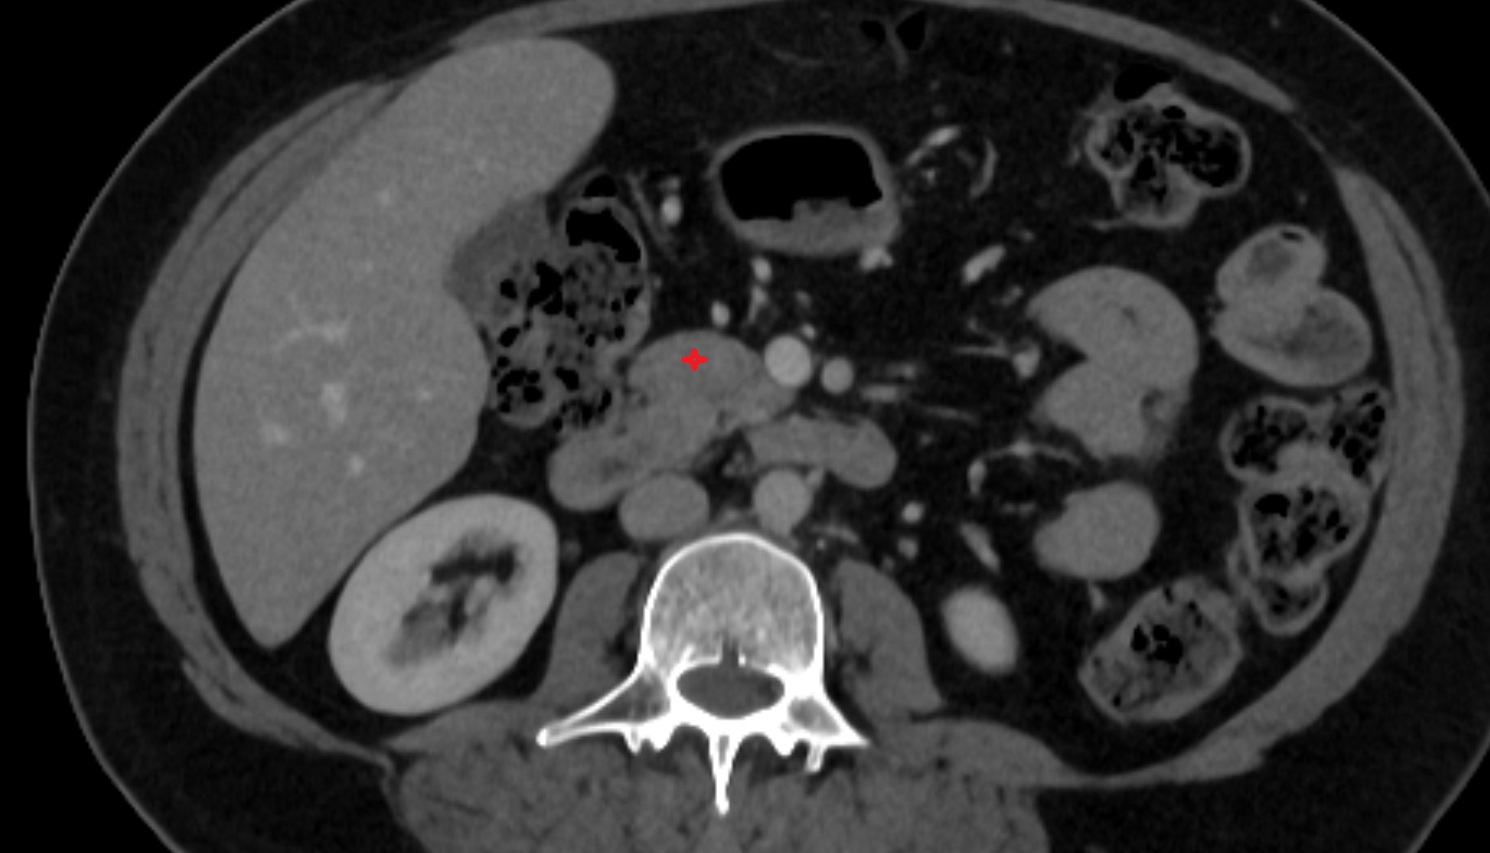

- kidneys

- Right kidney

- Left kidney

- Kidney cortex (Renal cortex)

- Renal medulla

- Renal pyramids

- Adrenal gland

- Renal artery

- Renal vein